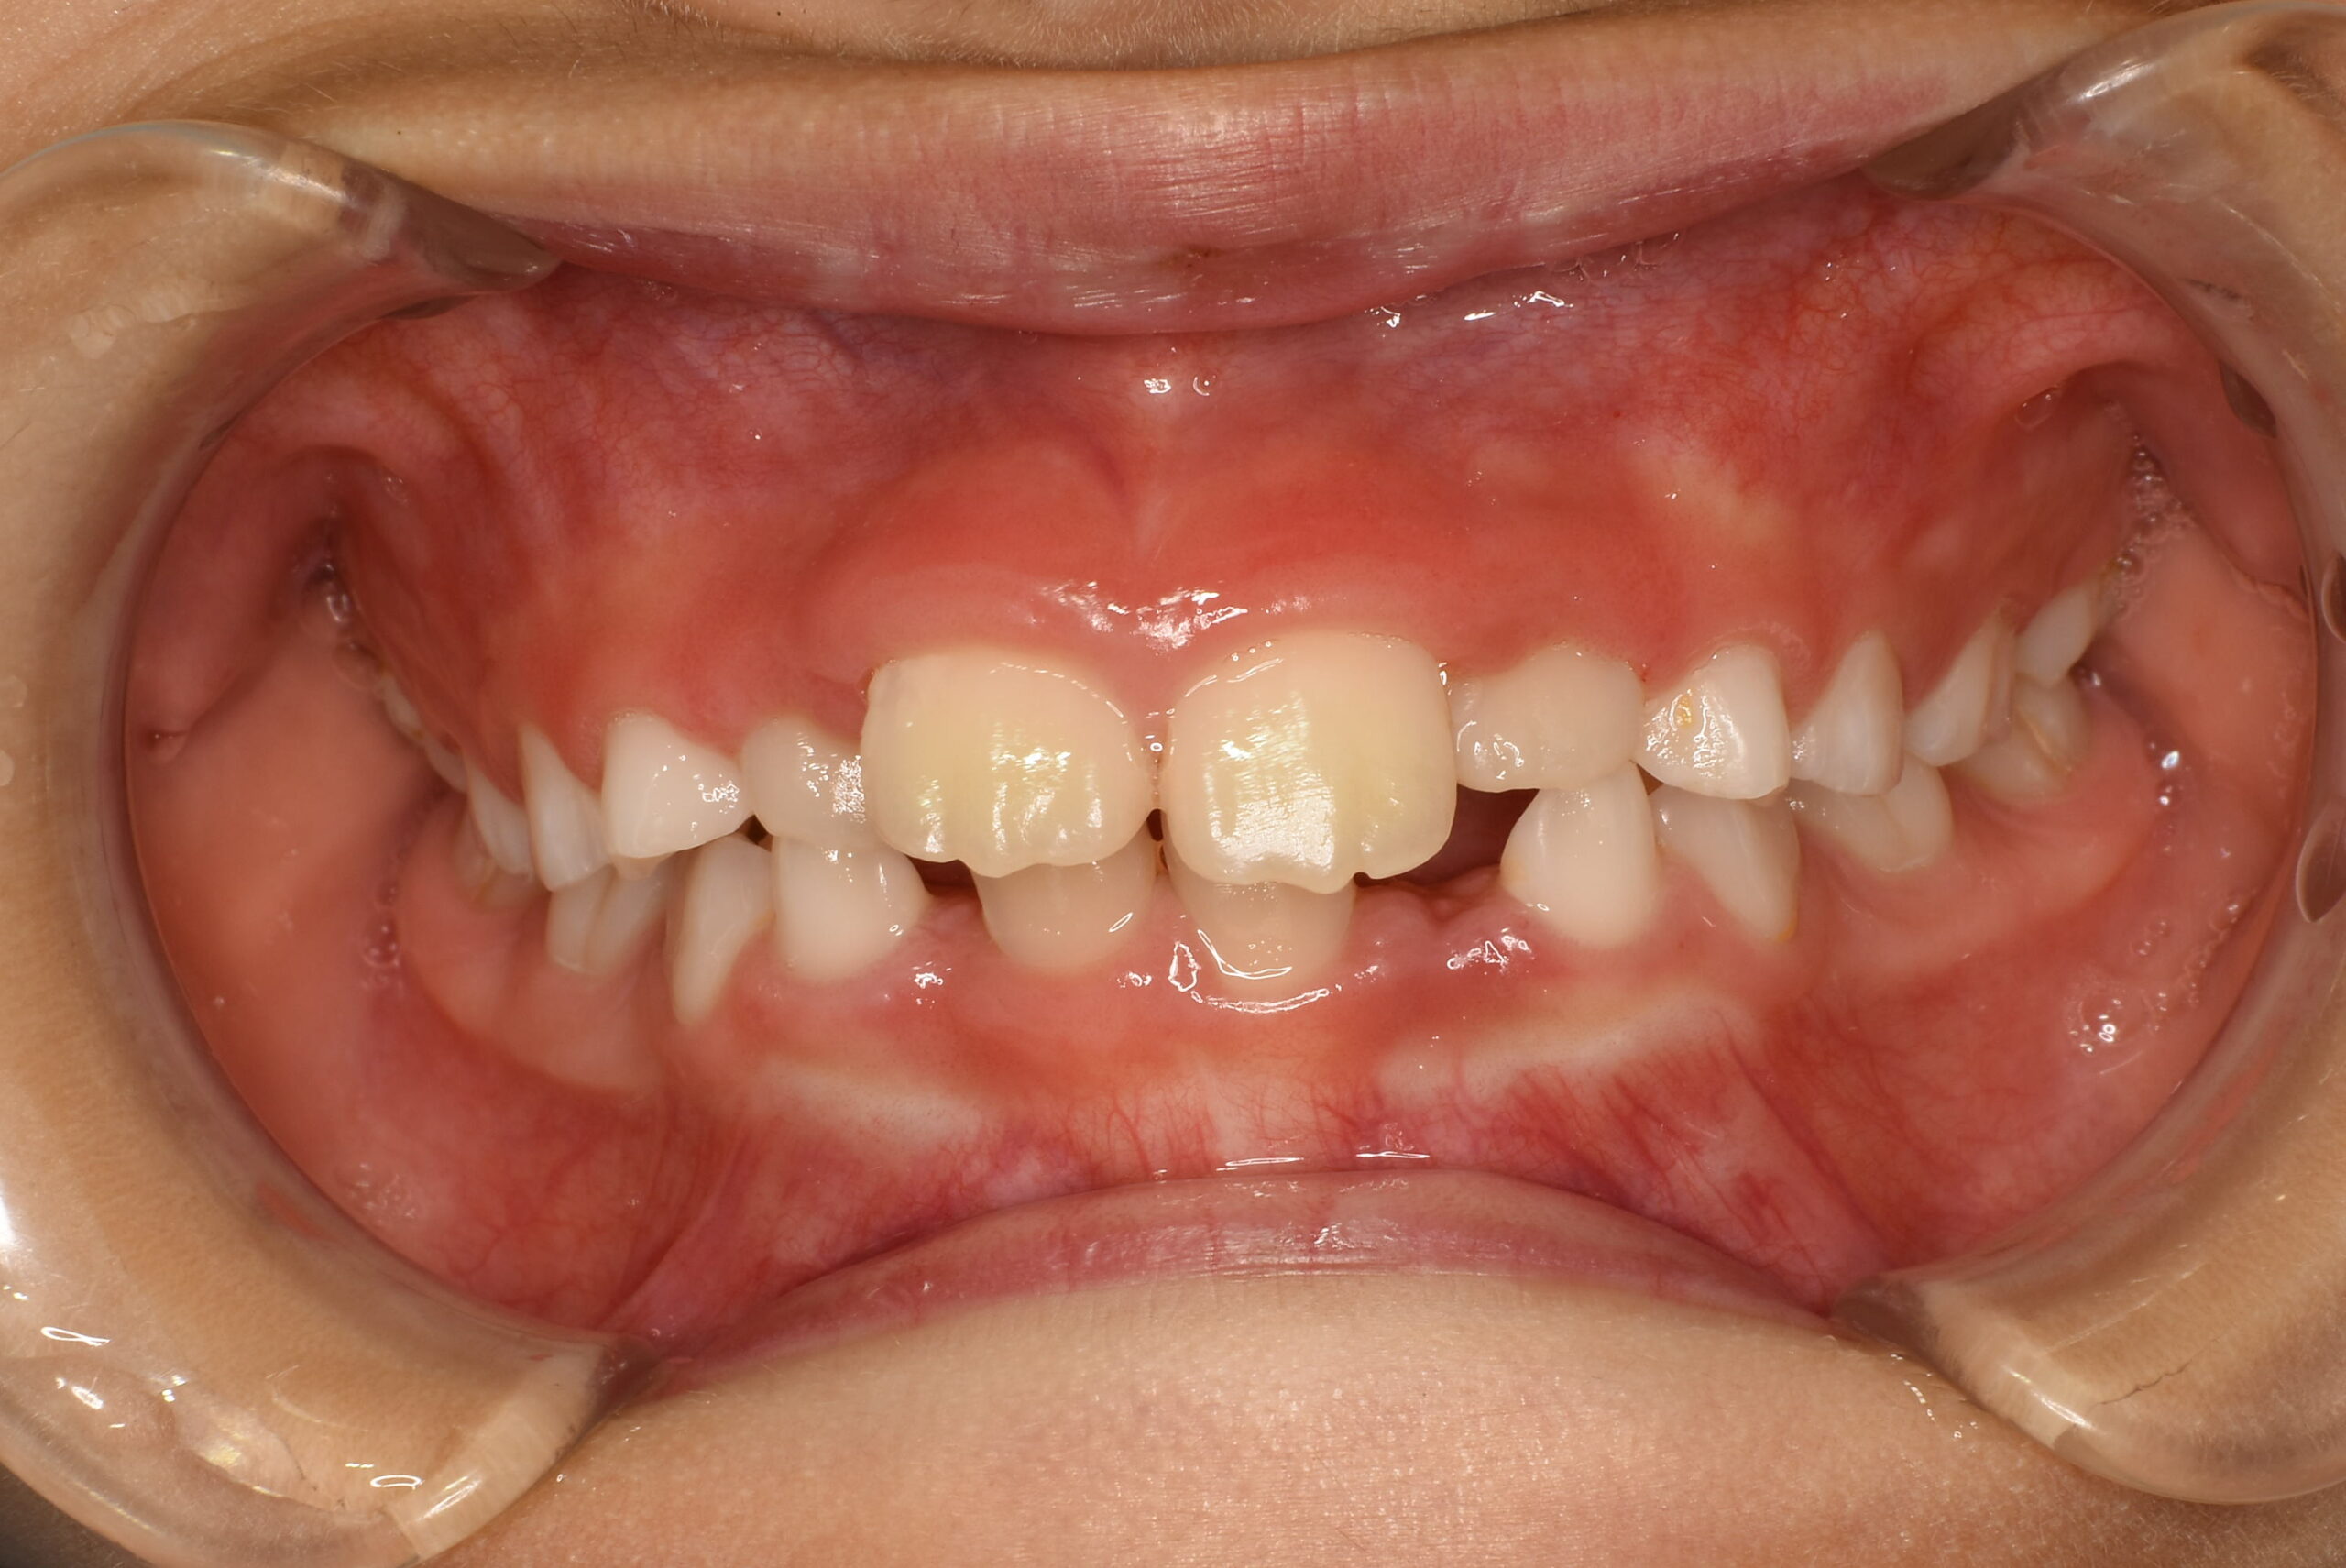

症例詳細:マイオブレースを用いた小児矯正(咬合誘導)

| 主訴 | 歯がバラバラに生えている(叢生) |

|---|---|

| 年齢・性別 | 女児・10歳(小学4年生) |

| 診断名 | 叢生(歯の生えるスペース不足)、口呼吸および舌の癖 |

| 治療内容 | 日中1時間と就寝時のマウスピース(マイオブレース)装着。あわせて呼吸・舌・飲み込み・唇を鍛えるアクティビティ(MFT)を毎日実施。 |

| 治療期間 | 2年2か月(現在も継続中) |

| 費用(税込) | 583,000円 ※検査代・装置代・月1回調整料5,500円含む |

| リスク・副作用 |

|

| 備考 | 本症例は治療途中の経過写真です。治療結果には個人差があります。 |